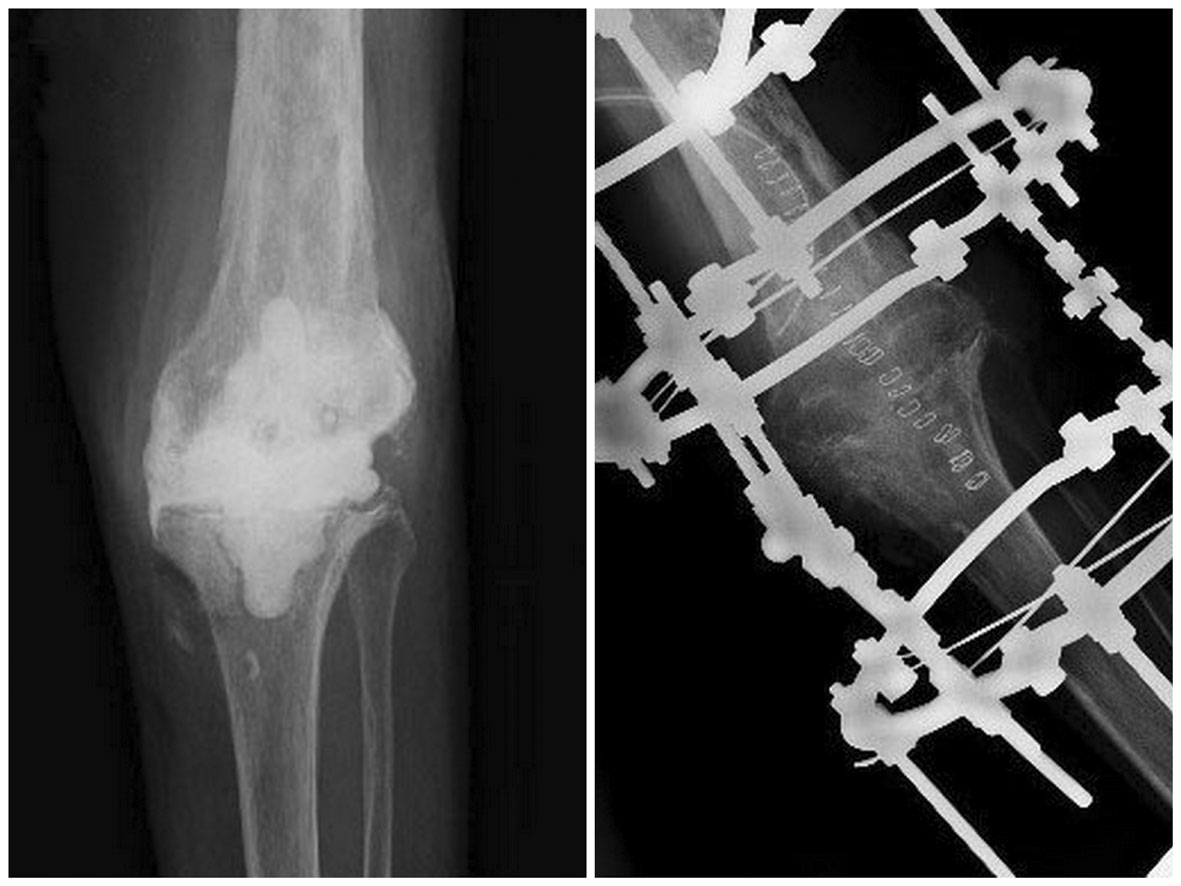

Prosthesis removal

The removal of prosthesis and surgical debridement is challenging and difficult. First at all is important to consider which surgical exposure to use before the operation. Isolated preexisting longitudinal approaches should be reused; in particular a well-healed medial parapatellar incision should always be used rather than making a new adjacent midline incision. In cases where more than one longitudinal incision are present is better to select the more lateral one (Figure 4), as blood supply entering from the medial side is significantly more than that entering from the lateral side. Revision incision should be long enough to provide wide exposure of distal femur and proximal tibia, and to allow extensive procedures if necessary. Intra-articular access could be in fact limited by a tight or compromised extensor mechanism. In these cases a lateral release or the snip of quadriceps tendon as described by Insall50 may be necessary to facilitate exposure. Patients with longstanding flexion contracture or extensile scars could require more aggressive exposure as tibial tubercle osteotomy.51 Once a sufficient exposure is obtained it is important to perform an extensive synoviectomy with debridement and removal of all prosthetic components and bone cement. The area of excision is sometimes widened slightly in areas where there are draining sinuses. The excision of all necrotic tissue is essential as well as complete excision of all pseudo membranes. As for aseptic revision, modular polyethylene is removed first in order to gain more space and reduce tension in the joint area. Even if could be difficult to remove a well fixed tibial component with the femoral component in place, attention should be paid to femur too. Thin osteotoms or small oscillating saw are ideal to get loose the femoral component before to use extraction tools or impactors. In case of extension stems, more elaborate procedures are needed especially in case of porous coated or cemented components, up to femoral transection (Figure 5). Osteotomes or saws are used to loosen the cement under a metal-backed tibial component. The removal is then completed by extractors or using the technique of stacked osteotoms.52 Reinsertion of a new prosthesis can then be performed as a direct exchange, the so called one stage reimplantation, or after a variable time delay, the two stage procedure.

Figure 4 Choice of the incision more laterally.

Figure 5 Knee prosthesis infection that need extensive tibial approach to explant long stem.